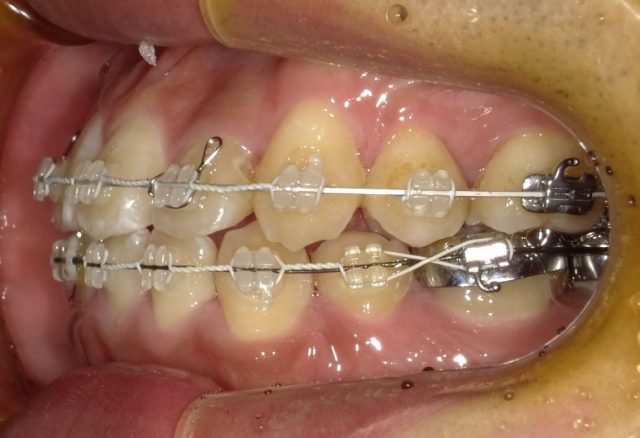

【右側面観】

【左側面観】